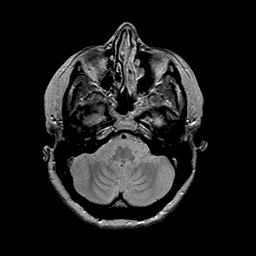

MR Study #2 -- Slice #13